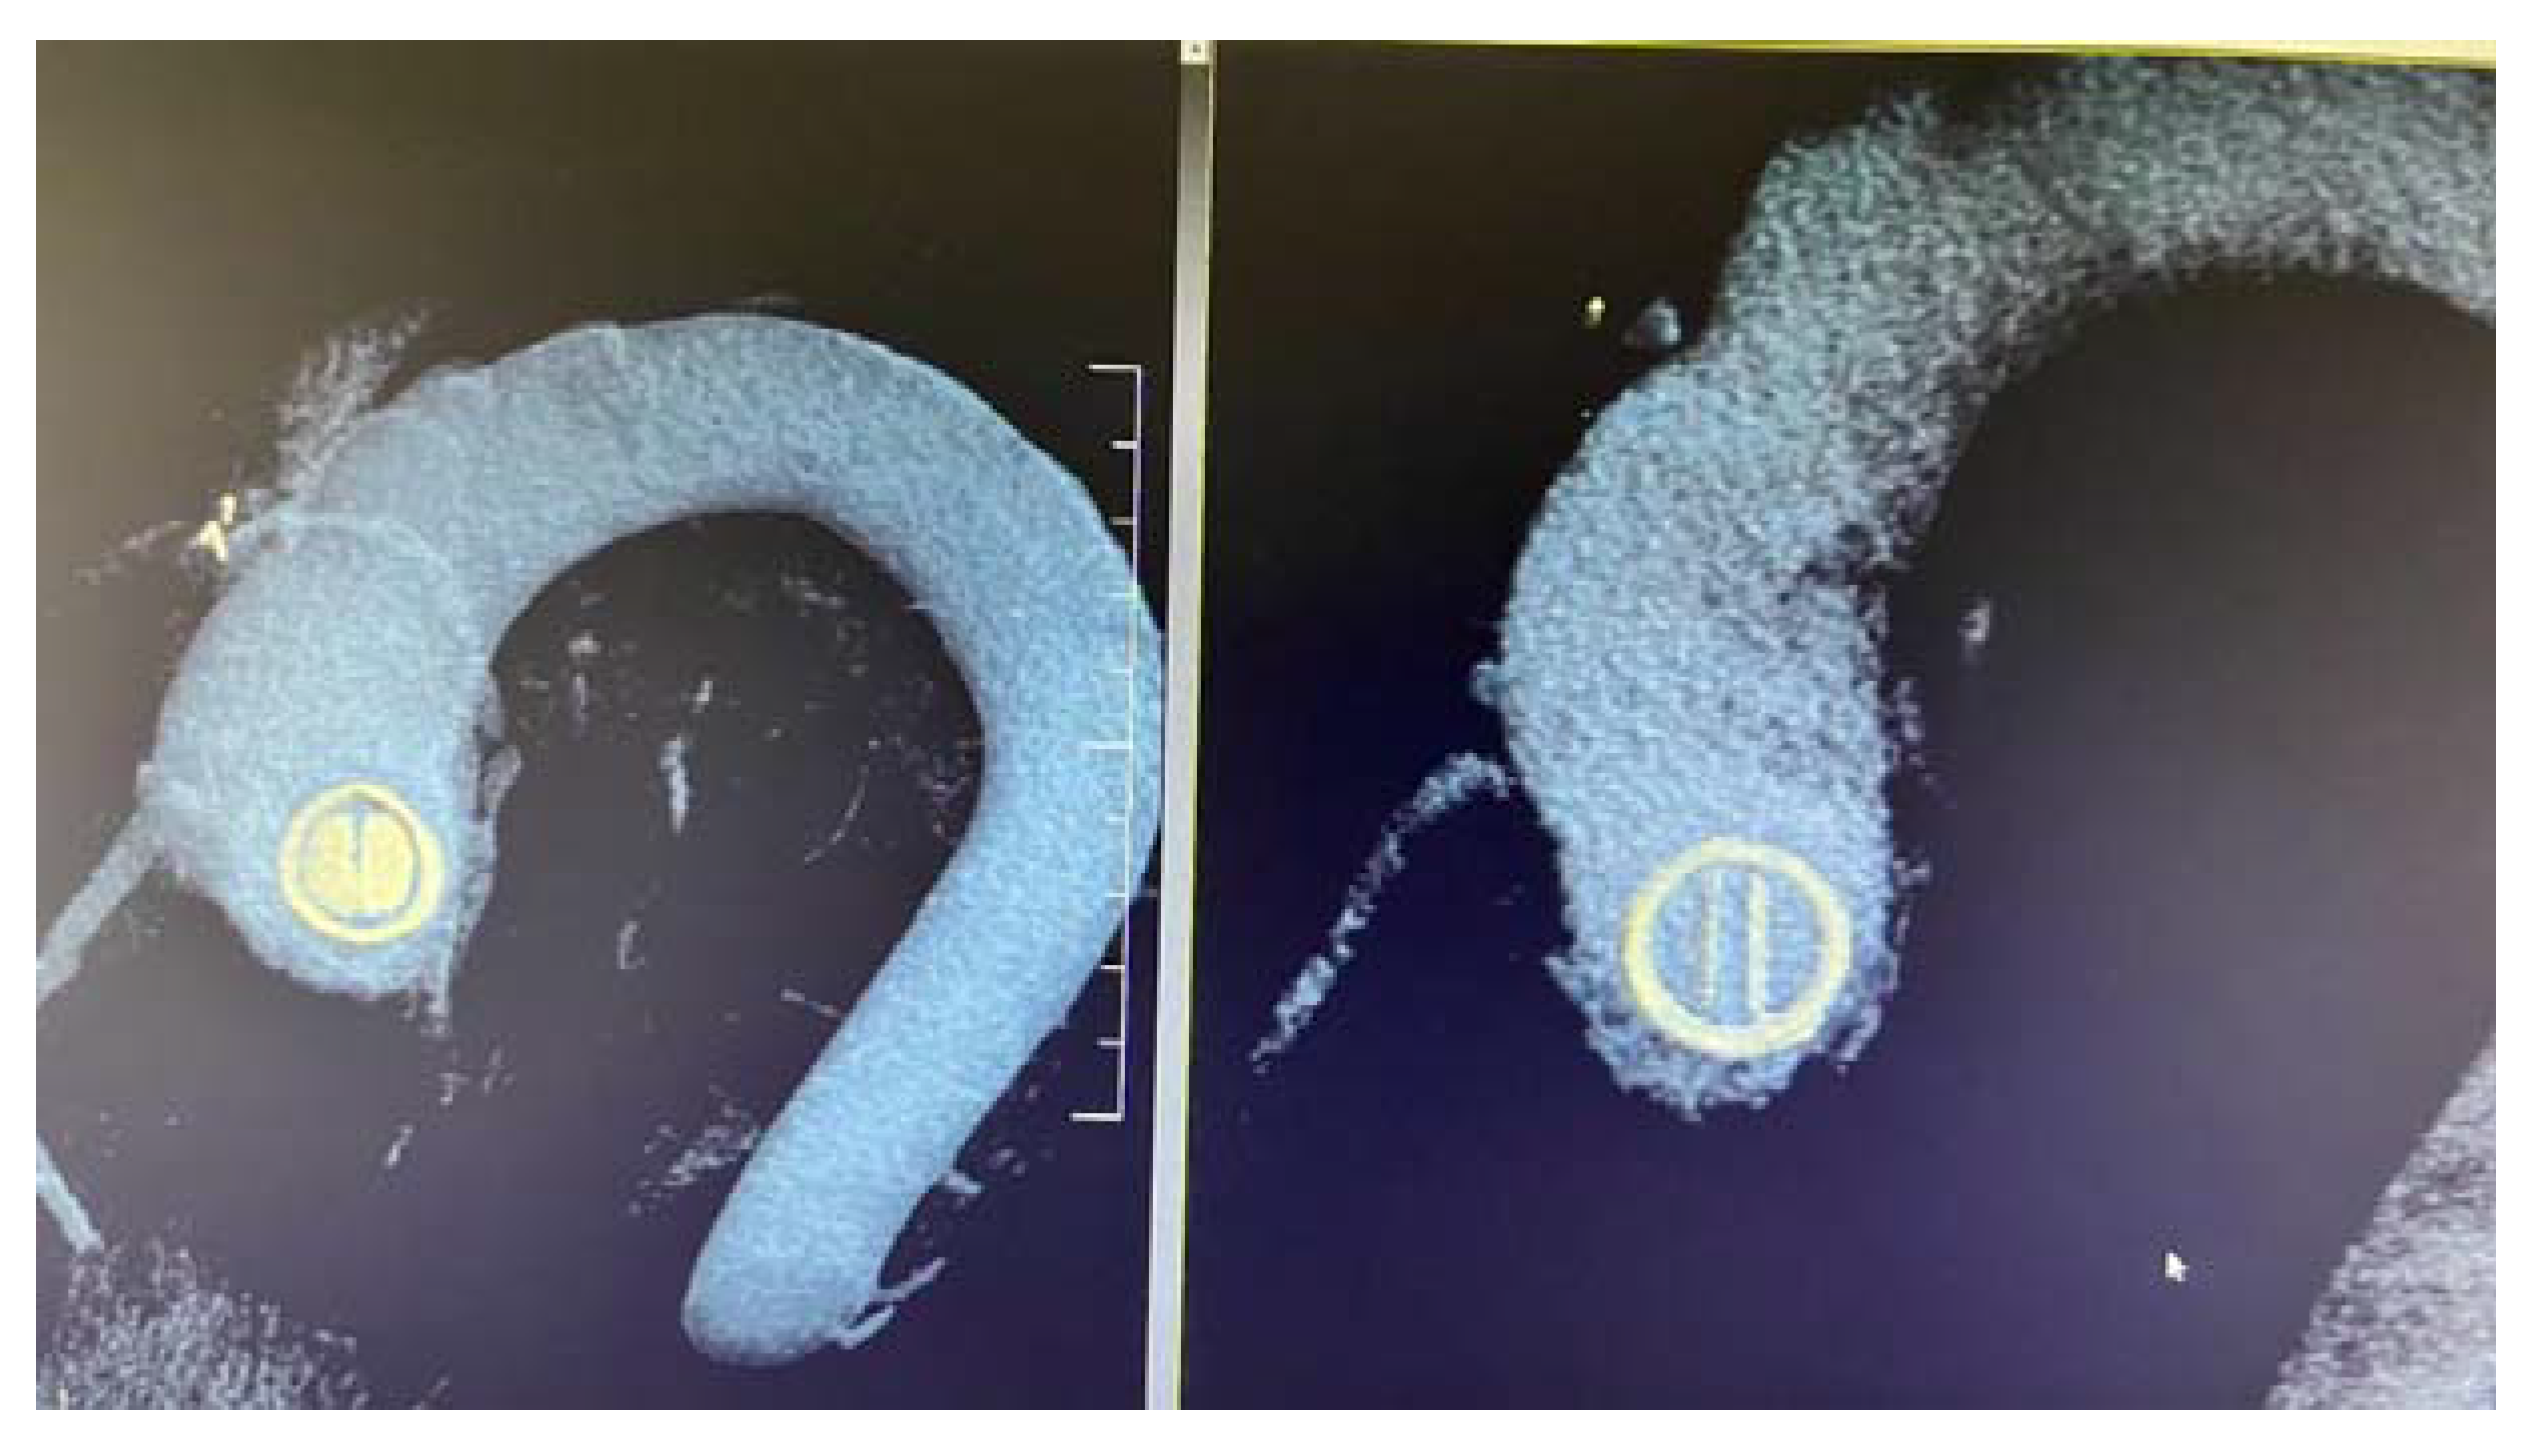

Moreover, 3D acquisitions can assist with the detection of silent thrombi that are present at the level of the prosthesis’ ring (Figure 8, panel B). In nonobstructive thrombi, where it is required to intensify anticoagulation and conduct rigorous monitoring, 3D TEE has a higher diagnostic value than 2D TEE [23,24,25,36,37,38,39].

Figure 8.

3D TEE with en face reconstruction of the mechanical mitral prosthesis with thrombus. (A) On disc (arrow). (B) On ring (arrow).